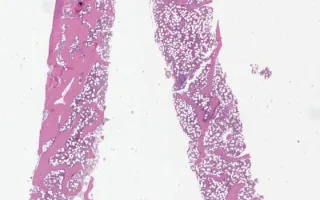

Bone Marrow, systemic mastocytosis, H&E stain

The accumulation of neoplastic populations of mast cells in the skin and other organs can lead to many different disease manifestations. The classic manifestation in the skin is urticaria pigmentosa (an itching rash and hyperpigmentation). The diagnosis of systemic mastocytosis is usually made by bone marrow biopsy.

Morphologically, dense infiltrates of mast cells(>=15 mast cells in aggregates) are detected in a section of bone marrow and >25% of the mast cells in the infiltrate are spindle-shaped or have atypical morphology. In this case, the patient’s manifestations are relatively limited, consistent with an indolent subvariant of systemic mastocytosis.

In this case the peripheral blood smear and bone marrow aspiration smear findings are unremarkable. The bone marrow biopsy shows aggregates of atypical mast cells. There are a few well-circumscribed non-paratrabecular lymphoid aggregates composed of a mixture of B and T-lymphocytes. Foci of moderate fibrosis are seen with a reticulin stain and they are associated with the mast cell and lymphoid aggregates. CD117 highlights scattered spindled mast cells which are also present in aggregates. The mast cells are positive for CD25 and mast cell tryptase and negative for CD2.

This slide shows H&E stain of the bone marrow biopsy. See Related Content for reticulin, CD25, CD117, tryptase, CD2, CD3 and CD20 stains. Peripheral blood smear and bone marrow aspiration smear (both unremarkable) are also shown.